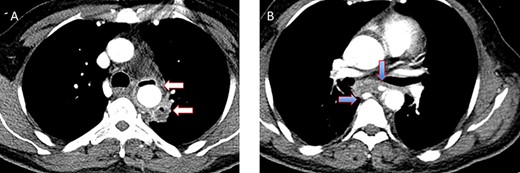

A 36-year-old male, involved in a minor motor vehicle accident while driving his car. He lost consciousness following a sudden onset of transient loss of vision which was not associated with palpitation or dizziness. His previous medical history revealed arterial hypertension and a corrected aortic coarctation with interposition graft at the age of 14. Pan CT scan was unremarkable except for thickening of the desending throacic aorta. His white blood count was very high (68 000 per cubic millimeter of blood). One day after the car accident, he developed nausea, hematemesis and melana. Upper GI endoscopy revealed blood in the stomach and distal esophafgus with no identifiable source of bleeding (Fig. 6). The patient developed massive hematemsis with hypotension requiring intubation and resuscitation. Another CT scan showed air pocket around distal aorta and contrast extravasation to the esophagus (Fig. 7). Another endoscopy revealed distal esophageal ulcer with clot extending toward the stomach (Fig. 8). AEF was suspected and then confirmed by aortogram. The fistula was treated by TEVAR (20 mm × 11.5 cm Valiant covered stent - Medtronic company, USA) followed by fully covered esophageal stent in the middle of the esophagus (Fig. 9).

(A) CT study with contrast showing gas adjacent to the descending thoracic aorta with thickened soft tissue around the esophagus. (B) Vascular contrast within the esophagus and projecting outside the aorta forming ‘pseudoaneurysm’ or penetrating aortic ulcer.